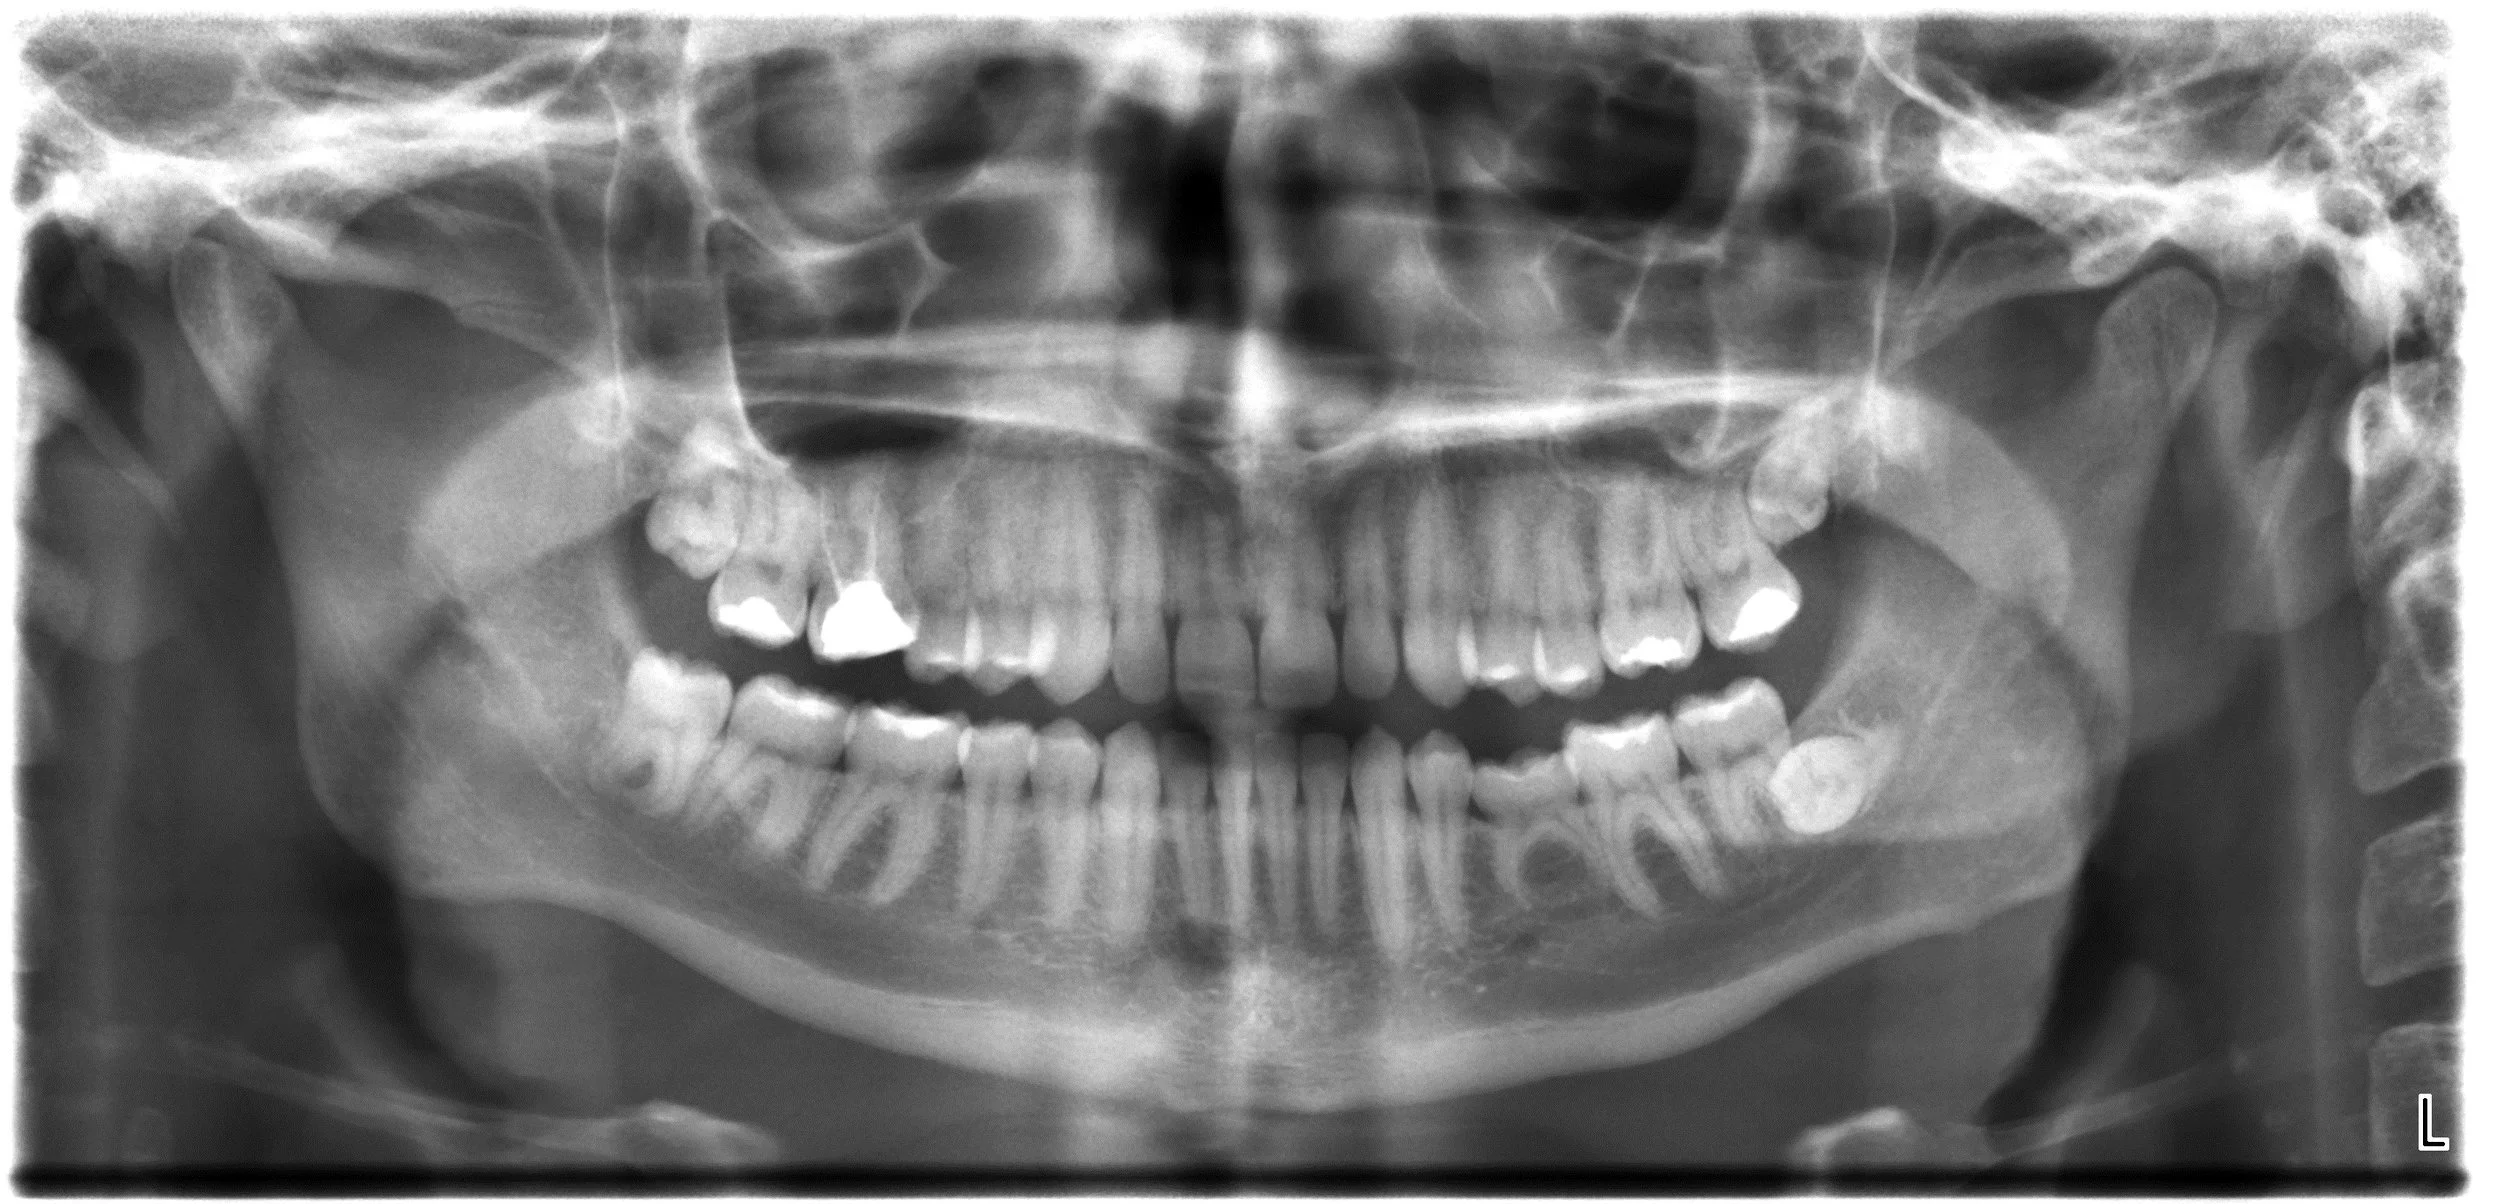

Fillings are used to restore original tooth structure following damage from cavities. Materials used can vary from ceramic to amalgam and can match original tooth colour and stability.

Crowns are are aesthetic restorations used to cap more severely damaged teeth. Crowns intricately crafted from either ceramic or porcelain to blend with the surrounding teeth.

Root Canals are procedures used to save an infected or damaged tooth by filling the inside cavity with biocompatible material.